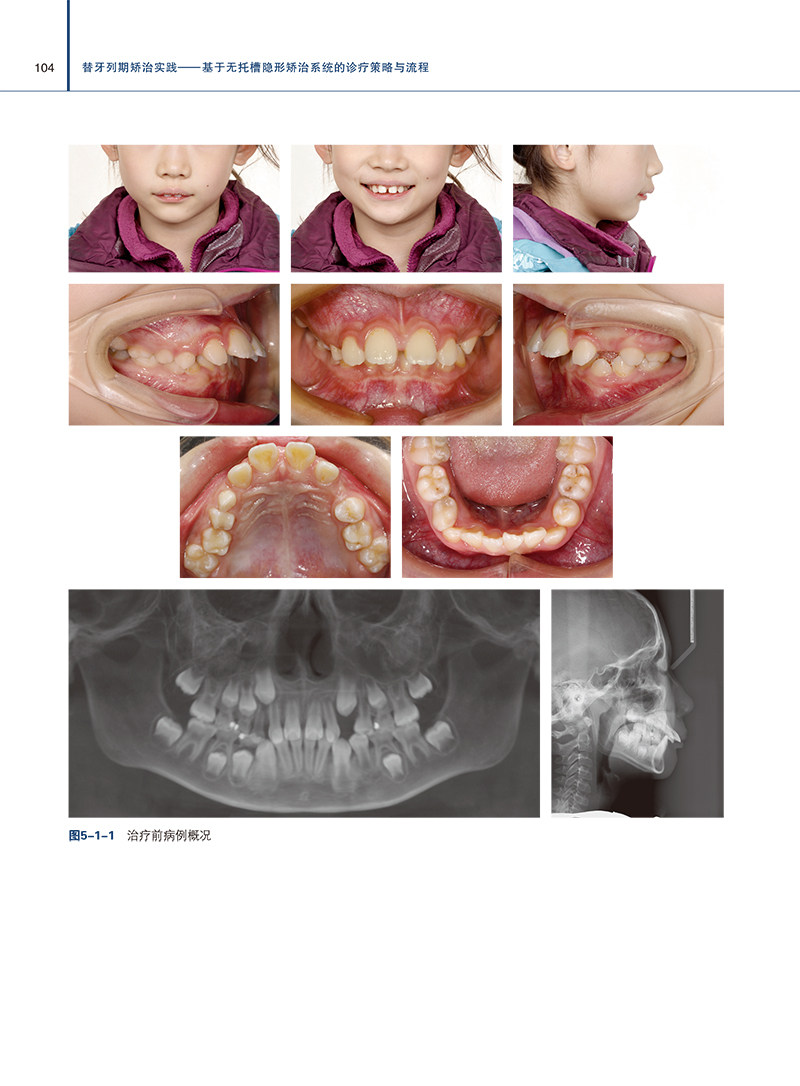

书名:替牙列期矫治实践 基于无托槽隐形矫治系统的诊疗策略与流程

作者:刘思琦